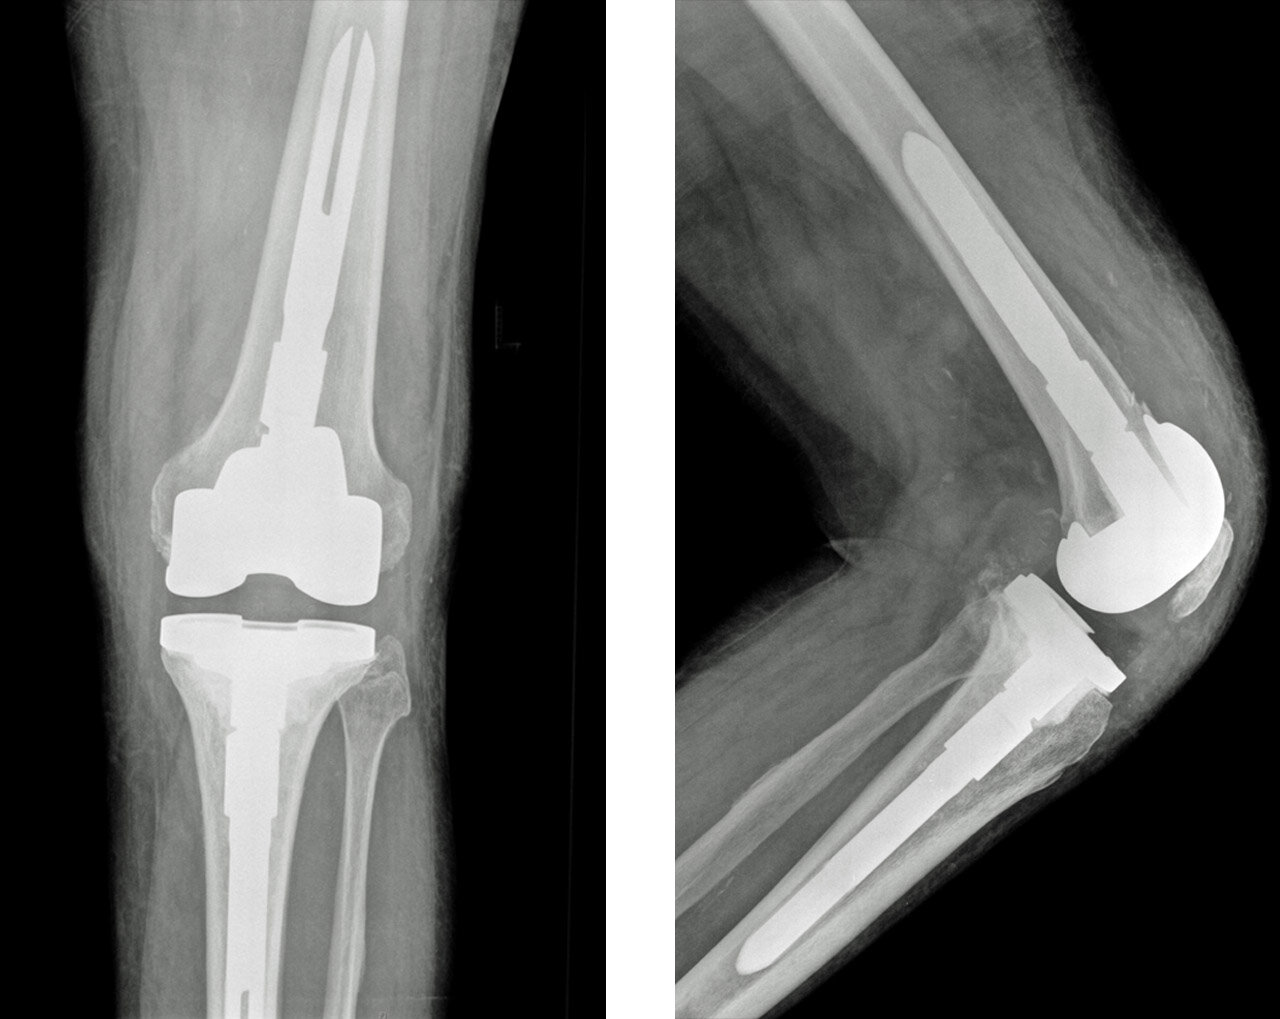

The X-Rays below show a 71 year old gentleman, who had an infected total knee replacement. He was treated with a two stage revision. Antibiotic loaded spacers where used after the infected knee replacement was removed. 3 months later, after the infection had settled, a new revision total knee replacement was performed.

In performing a revision, a special implants such as components with a stem and metal “augments” are used to address these difficulties. Most of the time all components are revised at the same time.

This patient’s knee X-Ray shows “lucent lines”, between the component and the bone, which is suggestive of loosening of the component. During a revision procedure the old components are removed and replaced by a system using stems and augments to accurately reconstruct the knee.